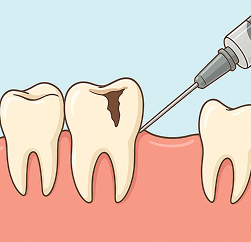

虫歯は進行性の疾患です。初期には自覚症状が乏しいため、気づいたときには神経まで達してしまっていることもあります。

虫歯は進行するほど治療が複雑になり、歯への負担も大きくなります。

早期に見つけることで、削る量を抑えたり、大がかりな処置を避けられる可能性が高まります。

エナメル質がに虫歯が進行した初期の虫歯です。痛みなどの自覚症状はほとんどなく、 この段階ではプラスチックの樹脂を使ったCR(コンポジットレジン)修復を行います。

C2は、虫歯がエナメル質を越えて象牙質まで進行した状態です。冷たい物や甘い物がしみるなどの症状がでます。